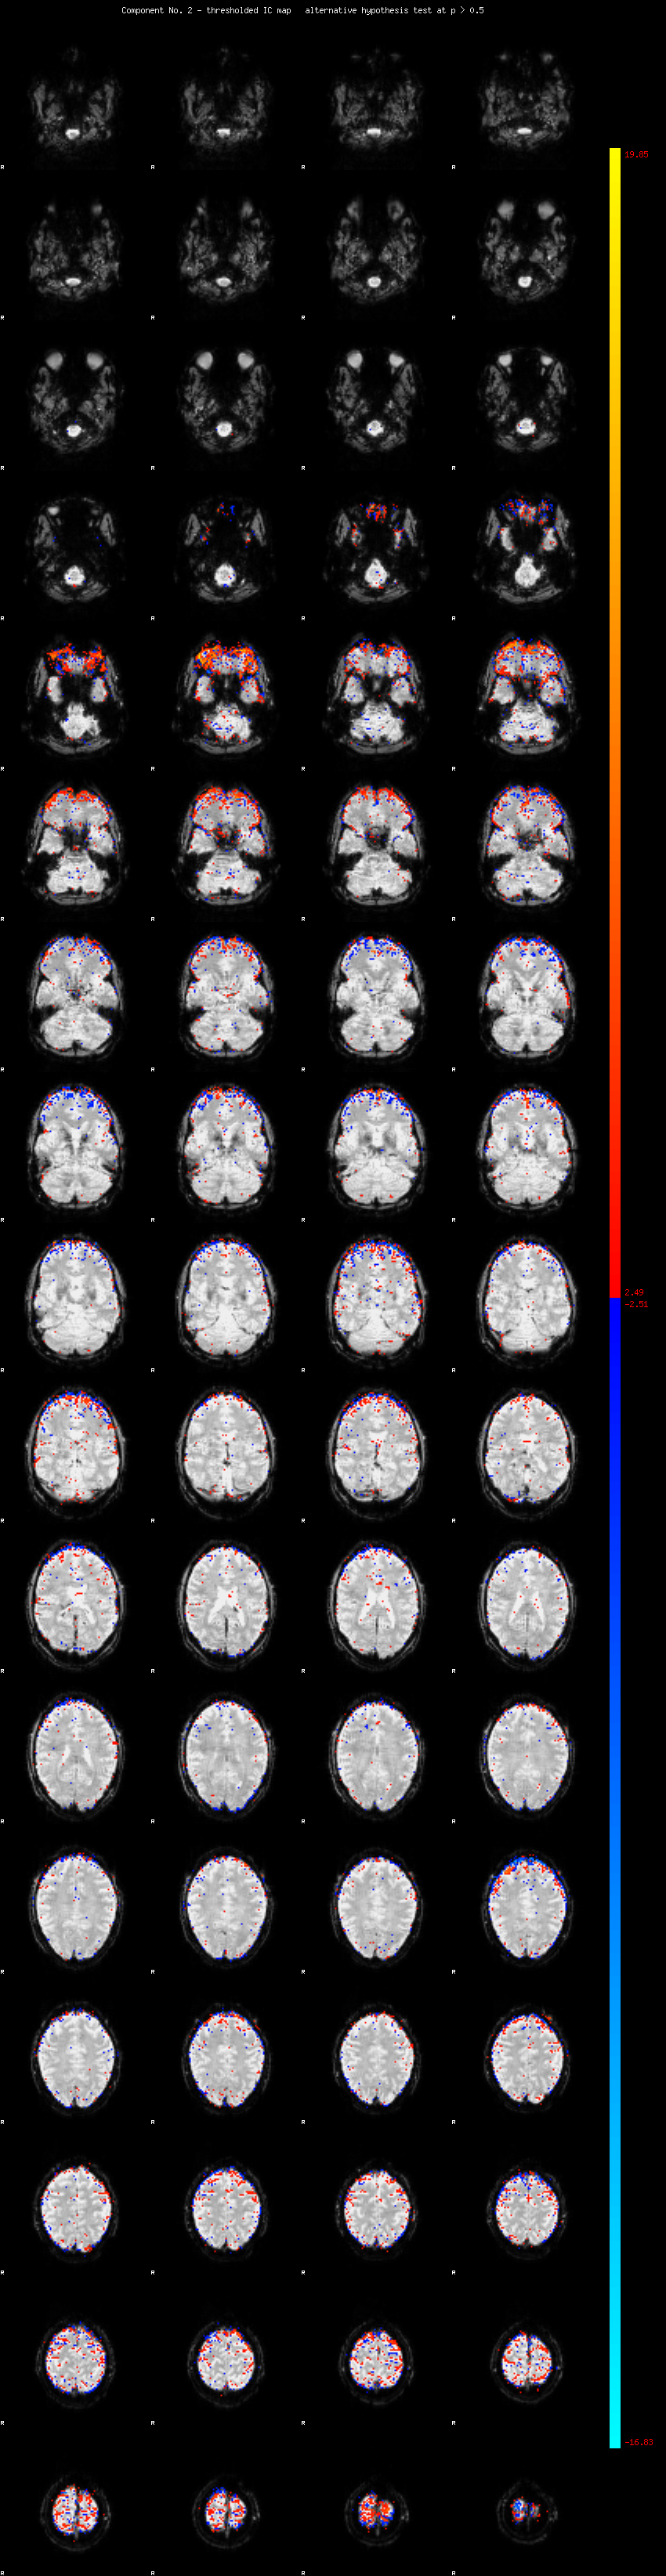

MELODIC Component 2

3.20 % of explained variance;     2.12 % of total variance